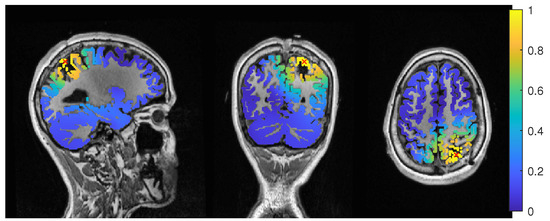

Except the cases of no regularization and average beamforming in the 6C head model, the differences of the evaluated methods in the distance to the resection volume for the MEG were overall lower than for the EEG. The event-related beamformer in both 6C and 3C head models showed localizations in the resection volume (localization distance of 0 mm) for the main part of evaluated regularization values. The 3C model’s localization distance increased slightly for the higher parameter value choices above 0.128. The 3C model’s power outside the resection was nearly the same as inside, resulting in a power relation close to 1, while the 6C model showed some certainty, with a power relation between 0.96 at low regularization values and 0.92 for high values. Both relations were not strongly affected by regularization. The localization of the 6C model at 0.05 regularization on the inside of the resection border is shown in Figure 5. While the maximum was inside the resection, the signal spread to the middle of the head to some degree.